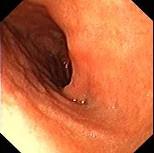

问题 女,36岁,上腹痛2年,伴嗳气、呃逆,弯腰时加重,查体未见特殊。胃镜如图,钡餐未:可见左侧隔上囊状阴影。最可能的诊断是 ( )

选项 A、幽门梗阻 B、反流性食管炎 C、胆石症 D、消化性溃疡 E、食管裂孔疝

答案 E